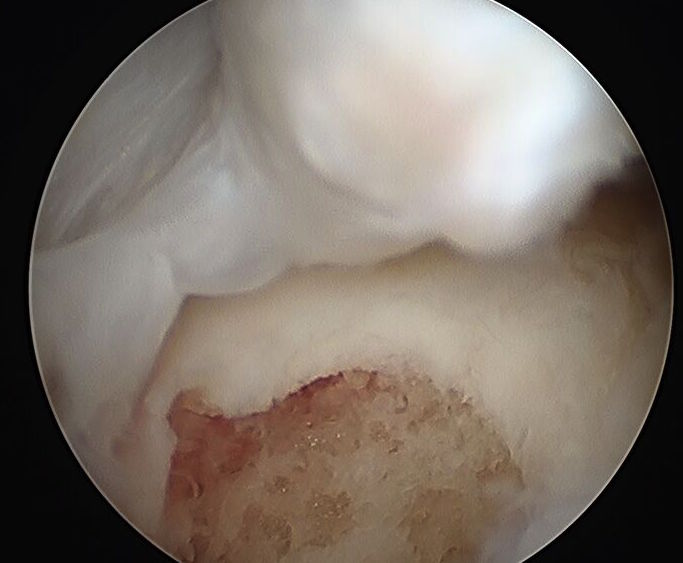

Very poor

- leads to mensical extrusion

- increased tibio-femoral contact pressure

- rapid early OA

- equivalent to total meniscectomy